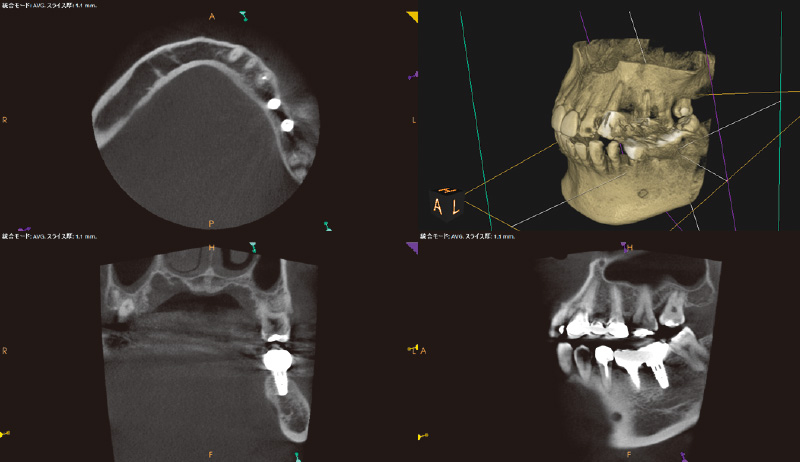

₆、₇にインプラントを埋入し左側の咬合を得る治療計画を立案。φ4.5長さ9.5mmのSPIイニセルインプラント エレメントRCを埋入した(図8)。まずはここで初期固定を得られたのでヒーリングキャップにて封鎖した(図9)。今回は勤務医たちへの指導の意味もあり、ガイデッドサージェリーにて行った。そして4週目でクローズドトレーにてシリコン印象を行い補綴装置をセットした(図10,11)。CBCT撮影を行い骨レベルの状態を確認し、機能的審美的にも問題ないことがわかっている(図12, 13)。

![[写真] 骨レベルの状態確認のためCBCT撮影](/academic/dentalmagazine/wp-content/uploads/sites/2/2025/09/194-8_photo12.jpg)

![[写真] 骨レベルの状態確認のためCBCT撮影](/academic/dentalmagazine/wp-content/uploads/sites/2/2025/09/194-8_photo13.jpg)